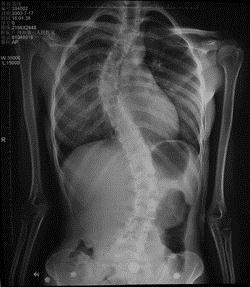

病历摘要: 患者××,女,17岁,发现剃刀背畸形3个月。查体:脊柱胸段向右侧凸,腰段向左侧凸,右胸廓呈剃刀背畸形,双下肢未见明显异常。该患者的治疗...

问题 病历摘要: 患者××,女,17岁,发现剃刀背畸形3个月。查体:脊柱胸段向右侧凸,腰段向左侧凸,右胸廓呈剃刀背畸形,双下肢未见明显异常。 该患者的治疗方案:

选项 A、手术矫正 B、先保守治疗,看无效再行手术治疗 C、保守治疗

答案 A